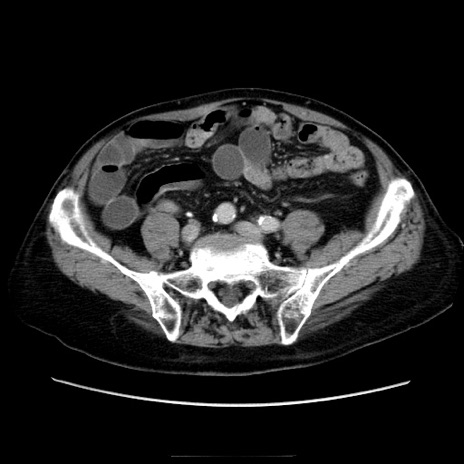

症例21(横断像)

【症例】70歳代男性

【主訴】腹痛

【現病歴】肝硬変・肝細胞癌にてかかりつけの方。約9時間前に食後より腹痛出現。症状が徐々に増悪し、嘔吐出現したため来院。

【既往歴】肝硬変、肝細胞癌(RFA、TACE後)

【身体所見】意識清明、表情苦悶様、BT 36℃、BP 129/78mmHg、P 88bpm、SpO2 97%(RA)、右上腹部から心窩部にかけて圧痛あり、反跳痛なし、筋性防御あり。

【データ】WBC 5800、CRP 0.16